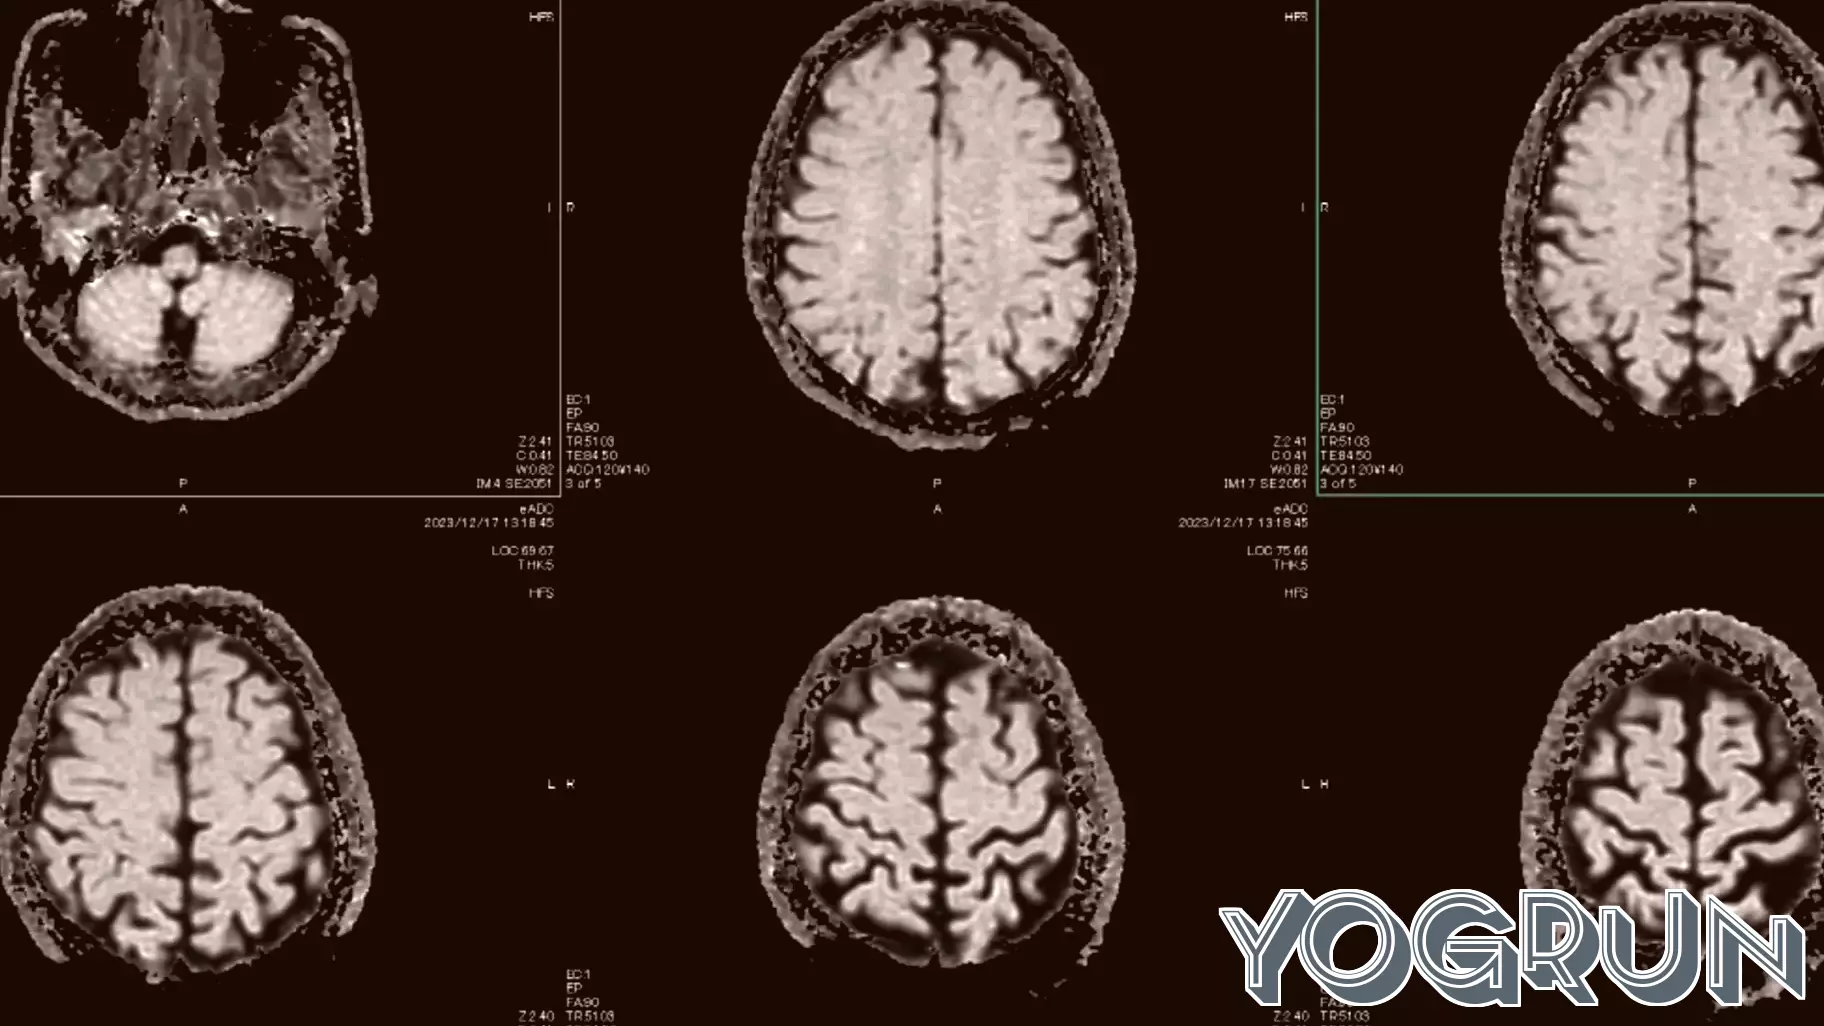

While AI systems demonstrate remarkable skill in analyzing medical images, predicting patient outcomes, and streamlining administrative tasks, their hardest test lies in the realm of trust and context. A diagnostic algorithm may be highly accurate on average, but can it account for a rare condition or a patient's unique history? The core issue shifts from pure performance to appropriate application.